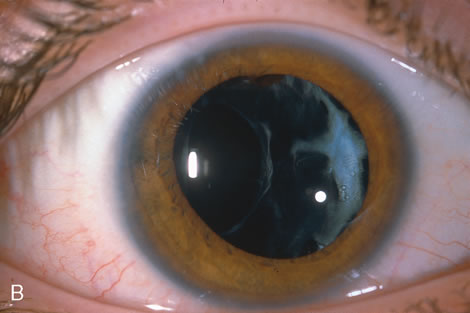

When the vitreous suction-cutting devices became available, they were quickly employed to remove cataracts in children. In addition to providing control of aspiration pressure and control of the flow of irrigation solutions, they also added the ability to remove some or all of the posterior lens capsule, even when the capsule had a thick fibrovascular stalk associated with persistent hyperplastic primary vitreous (PHPV) or a thick capsular plaque (Fig. 2). These fine-tip suction-cutting instruments provided sufficient control of the anterior chamber depth, thus permitting the surgeon to precisely open the posterior capsule and, if necessary, safely remove vitreous from the anterior chamber. Keech and co-workers,12 in a contemporaneous surgical series, showed that having the ability to remove the posterior lens capsule and perform an anterior vitrectomy reduced the need for secondary procedures from 75%, if the capsule was left intact, to 11% after capsulectomy and anterior vitrectomy. They found that when a large section of the posterior lens capsule was removed, it provided a lasting optical opening and reduced the requirement for additional surgery.

As techniques evolved, concerns were raised about the wisdom of removing a portion of the anterior vitreous with the capsulectomy. Occasional reports postulated that cystoid macular edema may occur with these techniques, but the actual risk of developing cystoid macular edema and the long-term results of an anterior vitrectomy on the eye of a child (and in particular on the retina) remain unknown.13 This relatively new capability of safely removing a portion of the lens capsule, or even the entire posterior lens capsule, gave rise to controversy. If only a small portion of the posterior capsule was removed, opacification could recur. Experience showed that the lens would develop pearls at the edge of the posterior capsulotomy, and these lens epithelial cells could migrate across a scaffold created by the anterior vitreous face. If the entire posterior lens capsule was removed, recurrence of posterior capsule opacification would usually not occur, but the barrier effect of the posterior lens capsule between the anterior chamber and vitreous was lost.

With the incremental acceptance of use of the IOL as the principal method of rehabilitating children's eyes, the issue of the formation of secondary membranes has become more complicated. Authors have advocated opening the posterior lens capsule at the time of the cataract surgery either by using vitrectors, or by performing a posterior lens capsule capsulorhexis, with or without prolapsing the lens optic through the posterior capsular opening.18–24 These measures however, do not ensure that the visual axis will not become opacified.25–27.